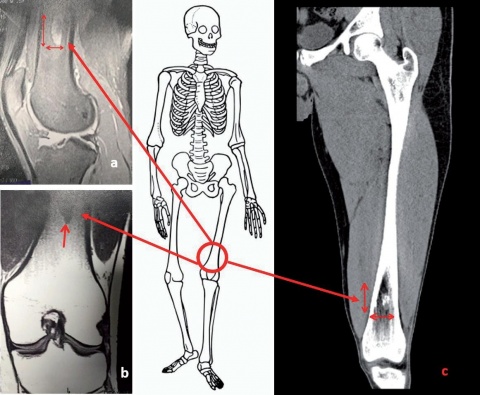

Fallbeispiel: Enchondrom

Zur Risikoklassifizierung von gutartigen Knochentumoren für die Beurteilung der allgemeinen Dienst- und Verwendungsfähigkeit von Soldaten Kevin Dallacker-Losensky¹, Magnus Scheer², Inken Seelmann¹, Michael Uhl³ ¹Sanitätsversorgungszentrum Volkach…